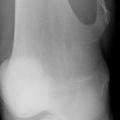

Processus lytique au sein de la métaphyse fémorale supérieure

TUMEURS OSSEUSES